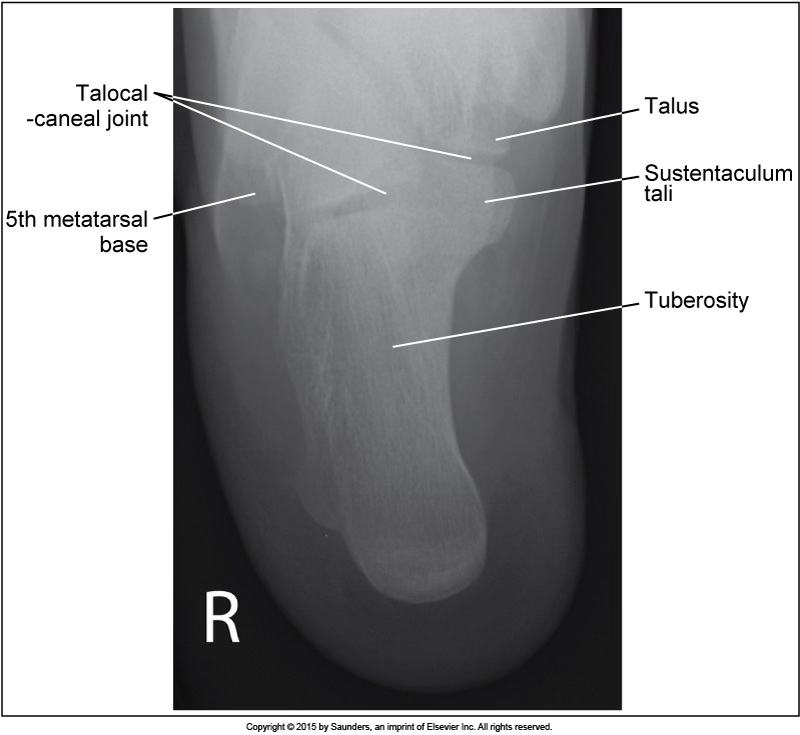

lateral calcaneus

accurate positioning

leg externally rotated

leg internally rotated